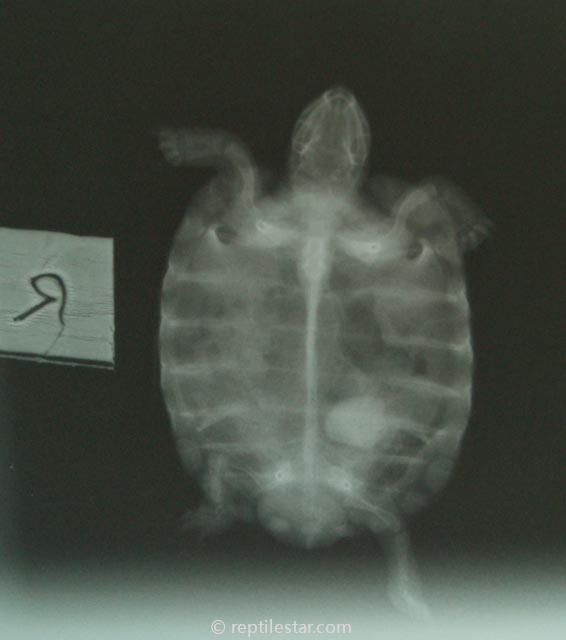

在这种环境中可能导致的后果如下图:

没错,这就是结石,触目惊心!